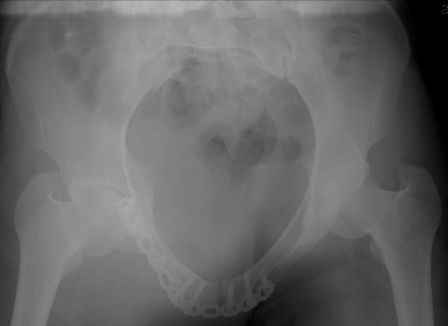

Спасибо за полезные советы! По inlet и outlet обнаружили перелом крестцас той-же стороны. Сегодня прооперировали реконструктивной пластиной с перекрытием симфиза, крестец, увы, фиксировать было нечем - оставили так (тем более, что грубой дислокации там нет). Рентгенограммы выложу позже.

Серия до- и послеоперационных снимков этой пациентки. Хотя бы post factum обсудить. Не знаю, что можно сделать с задними отделами стержневым аппаратом, но три крепких парня открытым путем с помощью "волшебных" слов еле-еле смогли отрепонировать - сзади все было очень ригидно!

я бы остановился на передней раме, операция - 30 мин, в таком варианте вроде бы репозиция - ничего, но когда давать нагрузку, ведь в лонном сочленении тоже есть подвижность? а если не давать - зачем операция?